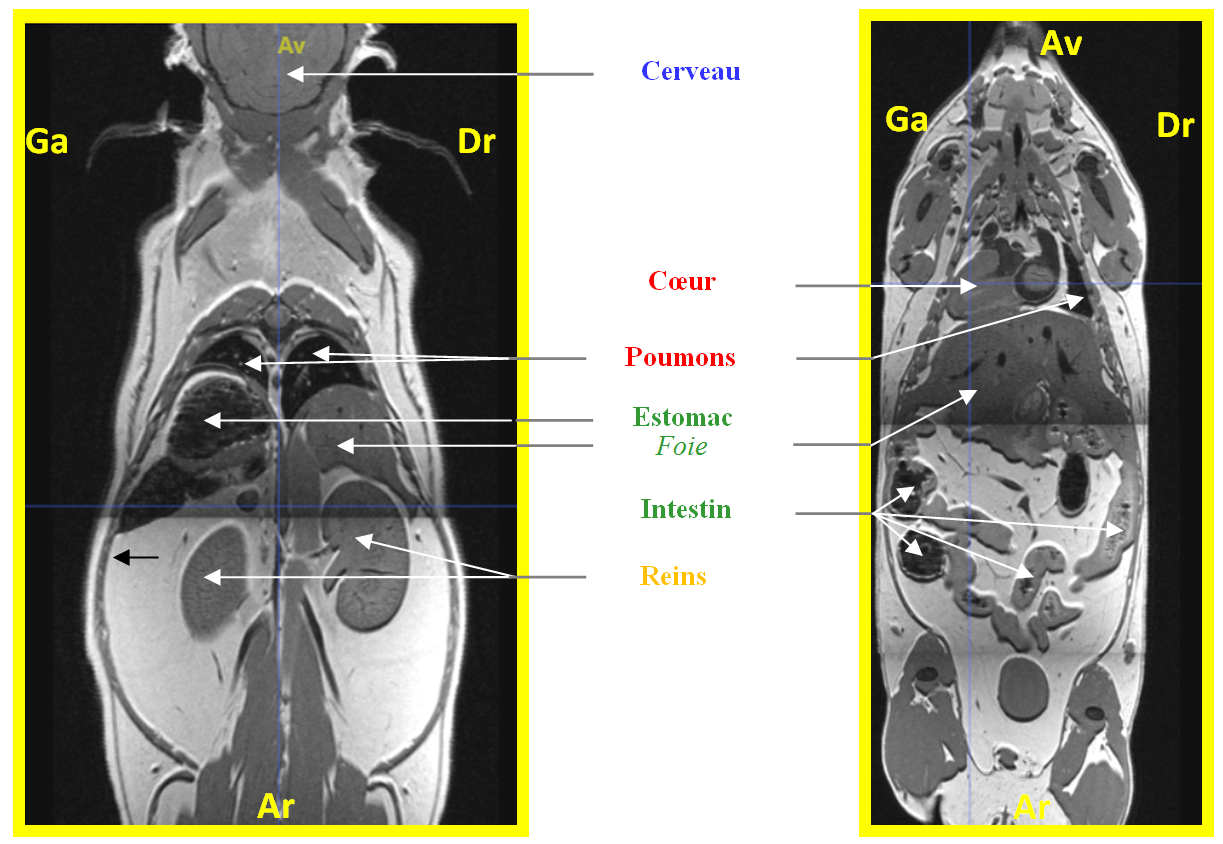

Souris coronal

Image dans sa taille originale :

784 ko